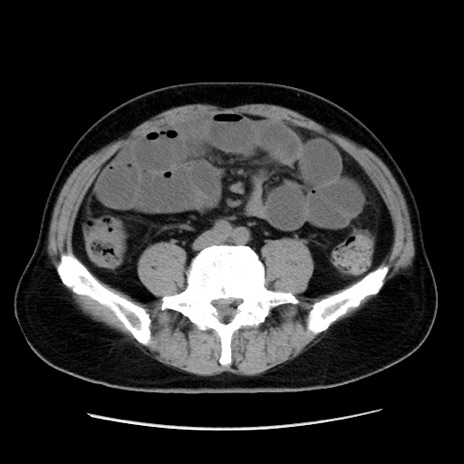

症例16(横断像)

【症例】 70歳代男性

【主訴】 腹痛、嘔吐

【現病歴】 約1ヶ月前より間欠的に腹痛と嘔吐あり、当院消化器内科を受診したところCTで多発する肝臓のLDAを指摘され、精査中であった。以降は消化器症状は安定していたが、2日前より嘔気と腹痛があり、同日より排便・排ガスが消失した。改善認めず、 本日、救急外来を受診した。

【既往歴】 大腸ポリープ切除後。

【身体所見】意識清明・会話良好、BT 36.3℃、BP 127/80mmHg、 P 80bpm、腹部:膨満あり、平坦・軟、上腹部正中および下腹部正中に圧痛あり、反跳痛なし、筋性防御なし。

【データ】WBC 7200、CRP 0.77